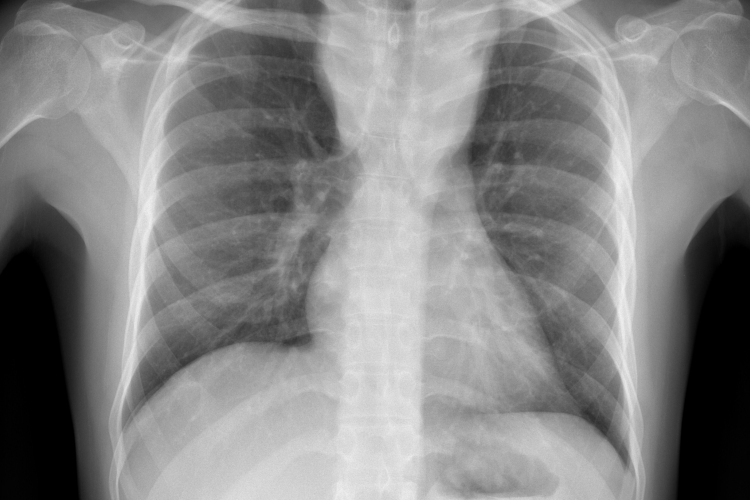

Csökkent a tbc-fertőzések száma Európában

Átlagosan 4,3 százalékkal csökkent az új tuberkulózisos (tbc-s) esetek száma 2010 és 2014 között az Egészségügyi Világszervezet (WHO) 53 országot magába foglaló európai régiójában.